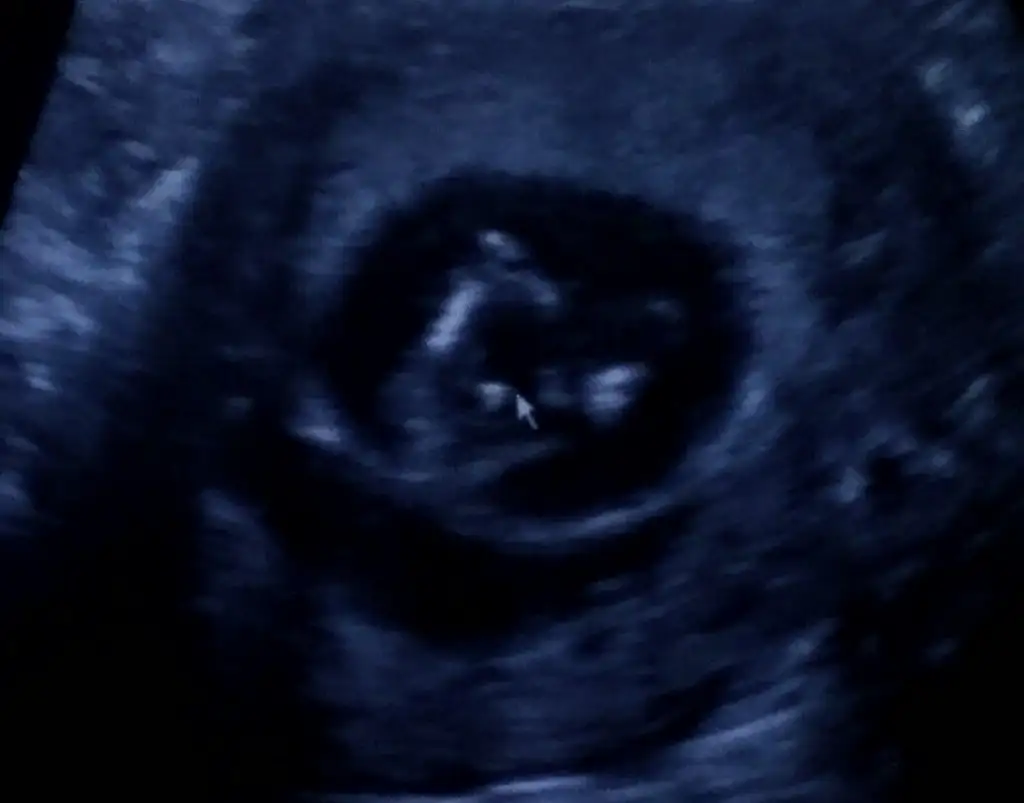

İyiyiz balım 10 haftalık olduk minnoşla büyüyoruz